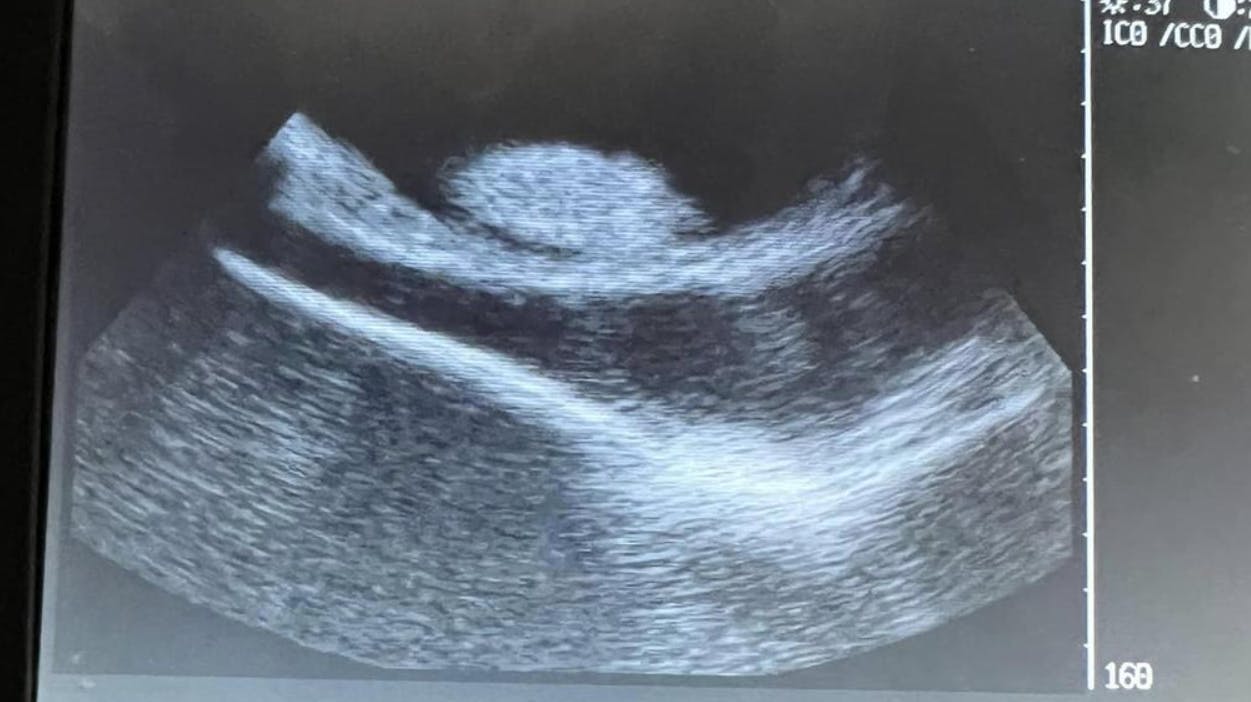

Hun er nemlig blevet ultralydsscannet ad flere omgange. Og her har personalet kunne se med egne øjne, at der altså ”svømmer” tre til fire små unger rundt inde i hendes mave.

Ungerne vokser støt, og derfor er det altså blot et spørgsmål om kort tid, før Charlotte bliver mor.